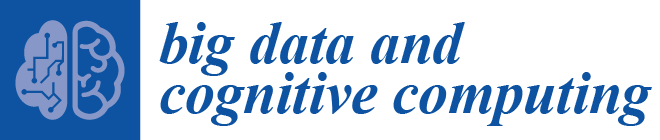

2.1.1. Kidney Tumors (KT)

2.1.4. Kidney Tumor Stage

- Computed Tomography (CT): In the kidney areas, widely used to assess the level of RCC. CT scans can help differentiate solid masses from cyst masses and reveal details about the patient’s tumor location, level, and progression to other organs. According to a previous study, tomographic CT imaging features may be used to diagnose patients with RCC by showing cytogenic variations between these cells [19,23,28].